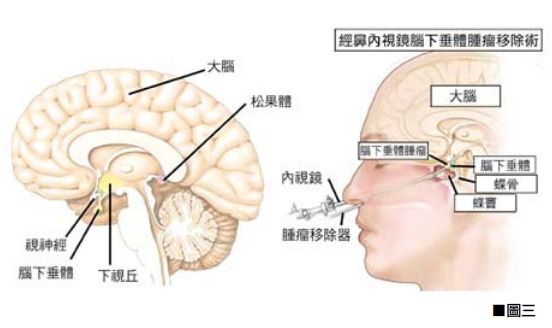

圖說01

所謂硬腦膜上出血是指,頭顱在受到撞擊後顱內血管受到創傷而流血,由於硬腦膜本身是保護腦部最外面的一層硬組織,倘若出血不是很嚴重則在傷後四至五天才會出現不尋常的劇烈頭痛。

圖說02

車禍或不慎跌倒撞到頭,別以為沒有流血或外傷就不必檢查診治,臨床上常見的腦內出血就是外表毫無傷口的腦創傷個案。